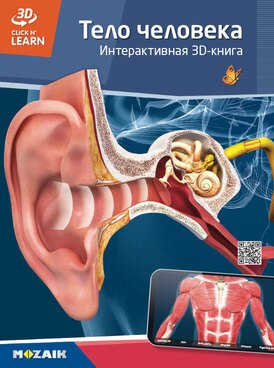

MS-6404-RU

Тело человека

Интерактивная 3D-книга

MS-6404-RU - Edición 2,

2023

64 páginas

Autores: Mozaik Education

В этой книге ты найдёшь важные и интересные факты об анатомии человека, о разнообразии органов чувств и пищевых особенностях, о продолжении рода человеческого и о многом другом.

27 EUR